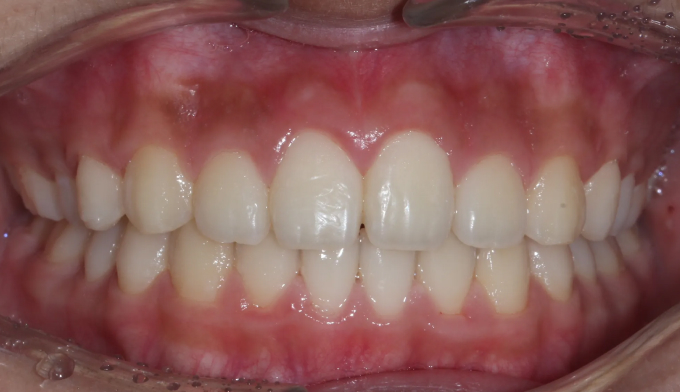

안모상으로 주걱턱 경향은 심해보이지 않고, 앞니의 약간의 반대교합만 관찰됩니다.

아래턱의 성장방향을 하방으로 바꿔주면서 상악의 전방견인을 시행하였습니다.

초등학교 2학년때부터 6학년때까지 진행되었습니다.